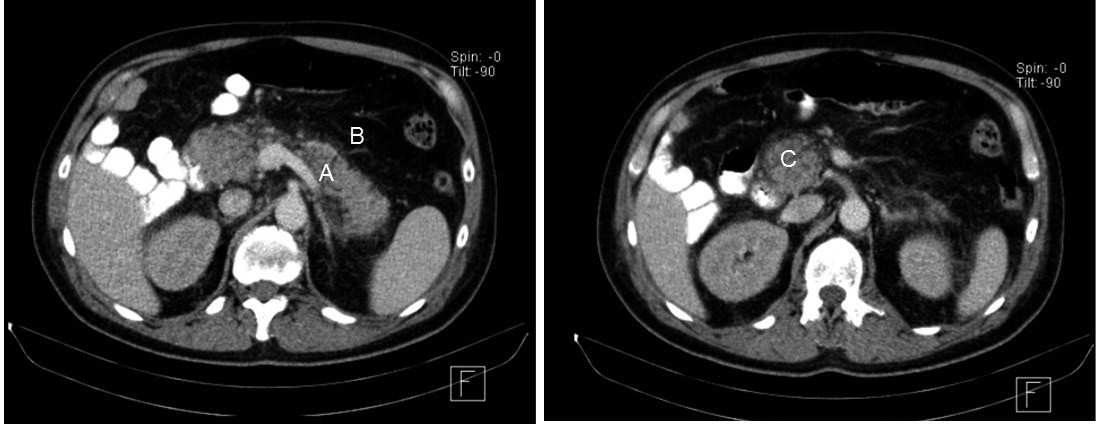

El paciente presentaba al ingreso alteraciones en los niveles de amilasa y lipasa séricas. El aumento por sobre tres desvíos estándar de los límites de referencia fue indicativo de una posible pancreatitis aguda (13), diagnóstico constatado mediante tomografía axial computada (Fig. 1).

En la ecografía de la glándula tiroides, se observó una lesión nodular sólida y heterogénea con una marcada vascularización central y periférica al Doppler de calor. Se complementó el hallazgo con una centellografía paratiroidea con Sestamibi-Tecnecio 99 (Fig. 2). En base a las pruebas de laboratorio e imágenes realizadas, se diagnosticó hiperparatiroidismo primario (HPP) por probable adenoma de paratiroides.

El tratamiento, en primera instancia, se basó en una terapéutica paliativa de urgencia enfocada en la restitución de la función renal y en la normalización de los niveles de Ca del paciente. Se indica un plan dinámico de hidratación en combinación con un diurético del asa (furosemida) asociado a bifosfonatos (pamidronato) (14). Dada la severidad del cuadro clínico y la refractariedad del mismo en las siguientes 24 h y debido a que el paciente no mostró recuperación de la función renal ni disminución de los niveles de Ca circulante, se emplea como siguiente terapéutica tratamiento sustitutivo renal con baño bajo en Ca (15). Como tratamiento definitivo de la lesión nodular, se realizó una paratiroidectomía. La biopsia del tejido analizado fue compatible con un score de adenoma paratiroideo (Fig. 3).